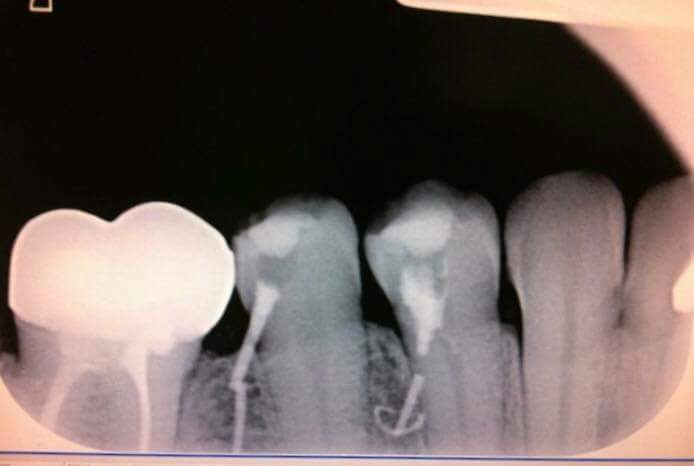

Et tu fais la radio en court de prepa... pour le gentil cdc.

Un cdc de la secu. Tous les ans 30 cas aleatoires oc endo pour un "petit" praticien radio post op (interpretation par une ia).